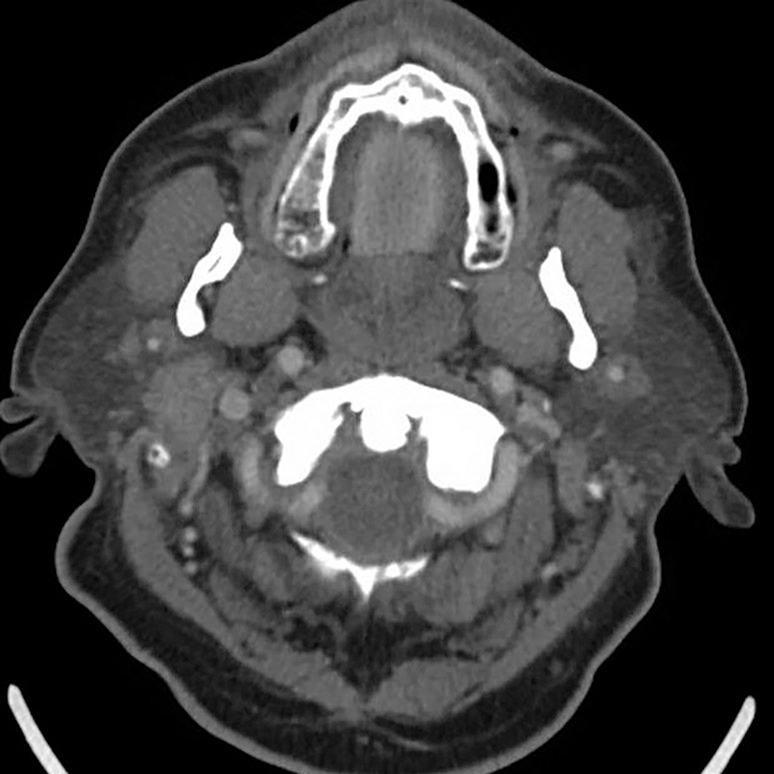

Presented live on Sunday, April 16 during the 2023 ARRS Annual Meeting in Honolulu, HI, our “The Suprahyoid Neck—Pathology Through Anatomy” Featured Session will focus on reviewing important anatomical subunits and common pathologies of the suprahyoid neck: the parapharyngeal, pharyngeal mucosal, masticator, parotid, carotid, retropharyngeal, danger, and perivertebral spaces (Fig. 1).

Speaking of studies, our illustrious Featured Sunday Session faculty are especially looking forward to leading breakout sessions regarding the various modalities most frequently found in imaging the suprahyoid neck. The comparative insensitivity of CT for artifacts, CT’s more comprehensive delineation of facial structures, and the promise of contrast-enhanced images to reveal critical vasculature continue to make CT more advantageous than ultrasound guidance (Fig. 2).